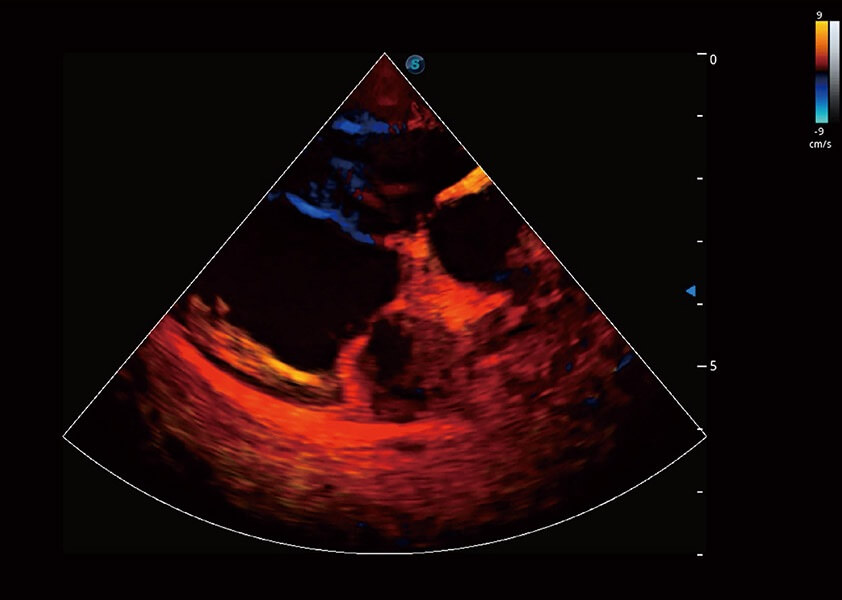

ProPet 60 作为一款高端台式动物超声设备,为动物医生的日常诊断提供了一系列贴合动物临床需求、解决临床实际问题的高级成像功能。凭借全系列高清探头,满足医生对腹部、心脏、生殖、浅表、肌骨等成像的所有需求,切实帮助您提升检查效率,提高诊断信心。

兽用彩色多普勒超声诊断系统

动物是人类最亲密的朋友和最值得信赖的伙伴。玖鼎集团也一直致力于探索动物专用的超声影像解决方案。 全新推出的ProPet系列,是玖鼎集团在动物超声影像智能化、专业化、精准化的一次跨越式革新。动物不能用言语来表述自己的不适,通过超声影像,ProPet系列搭建了动物医生与不同物种沟通的“桥梁”,为动物医生注入了“治愈之力”。